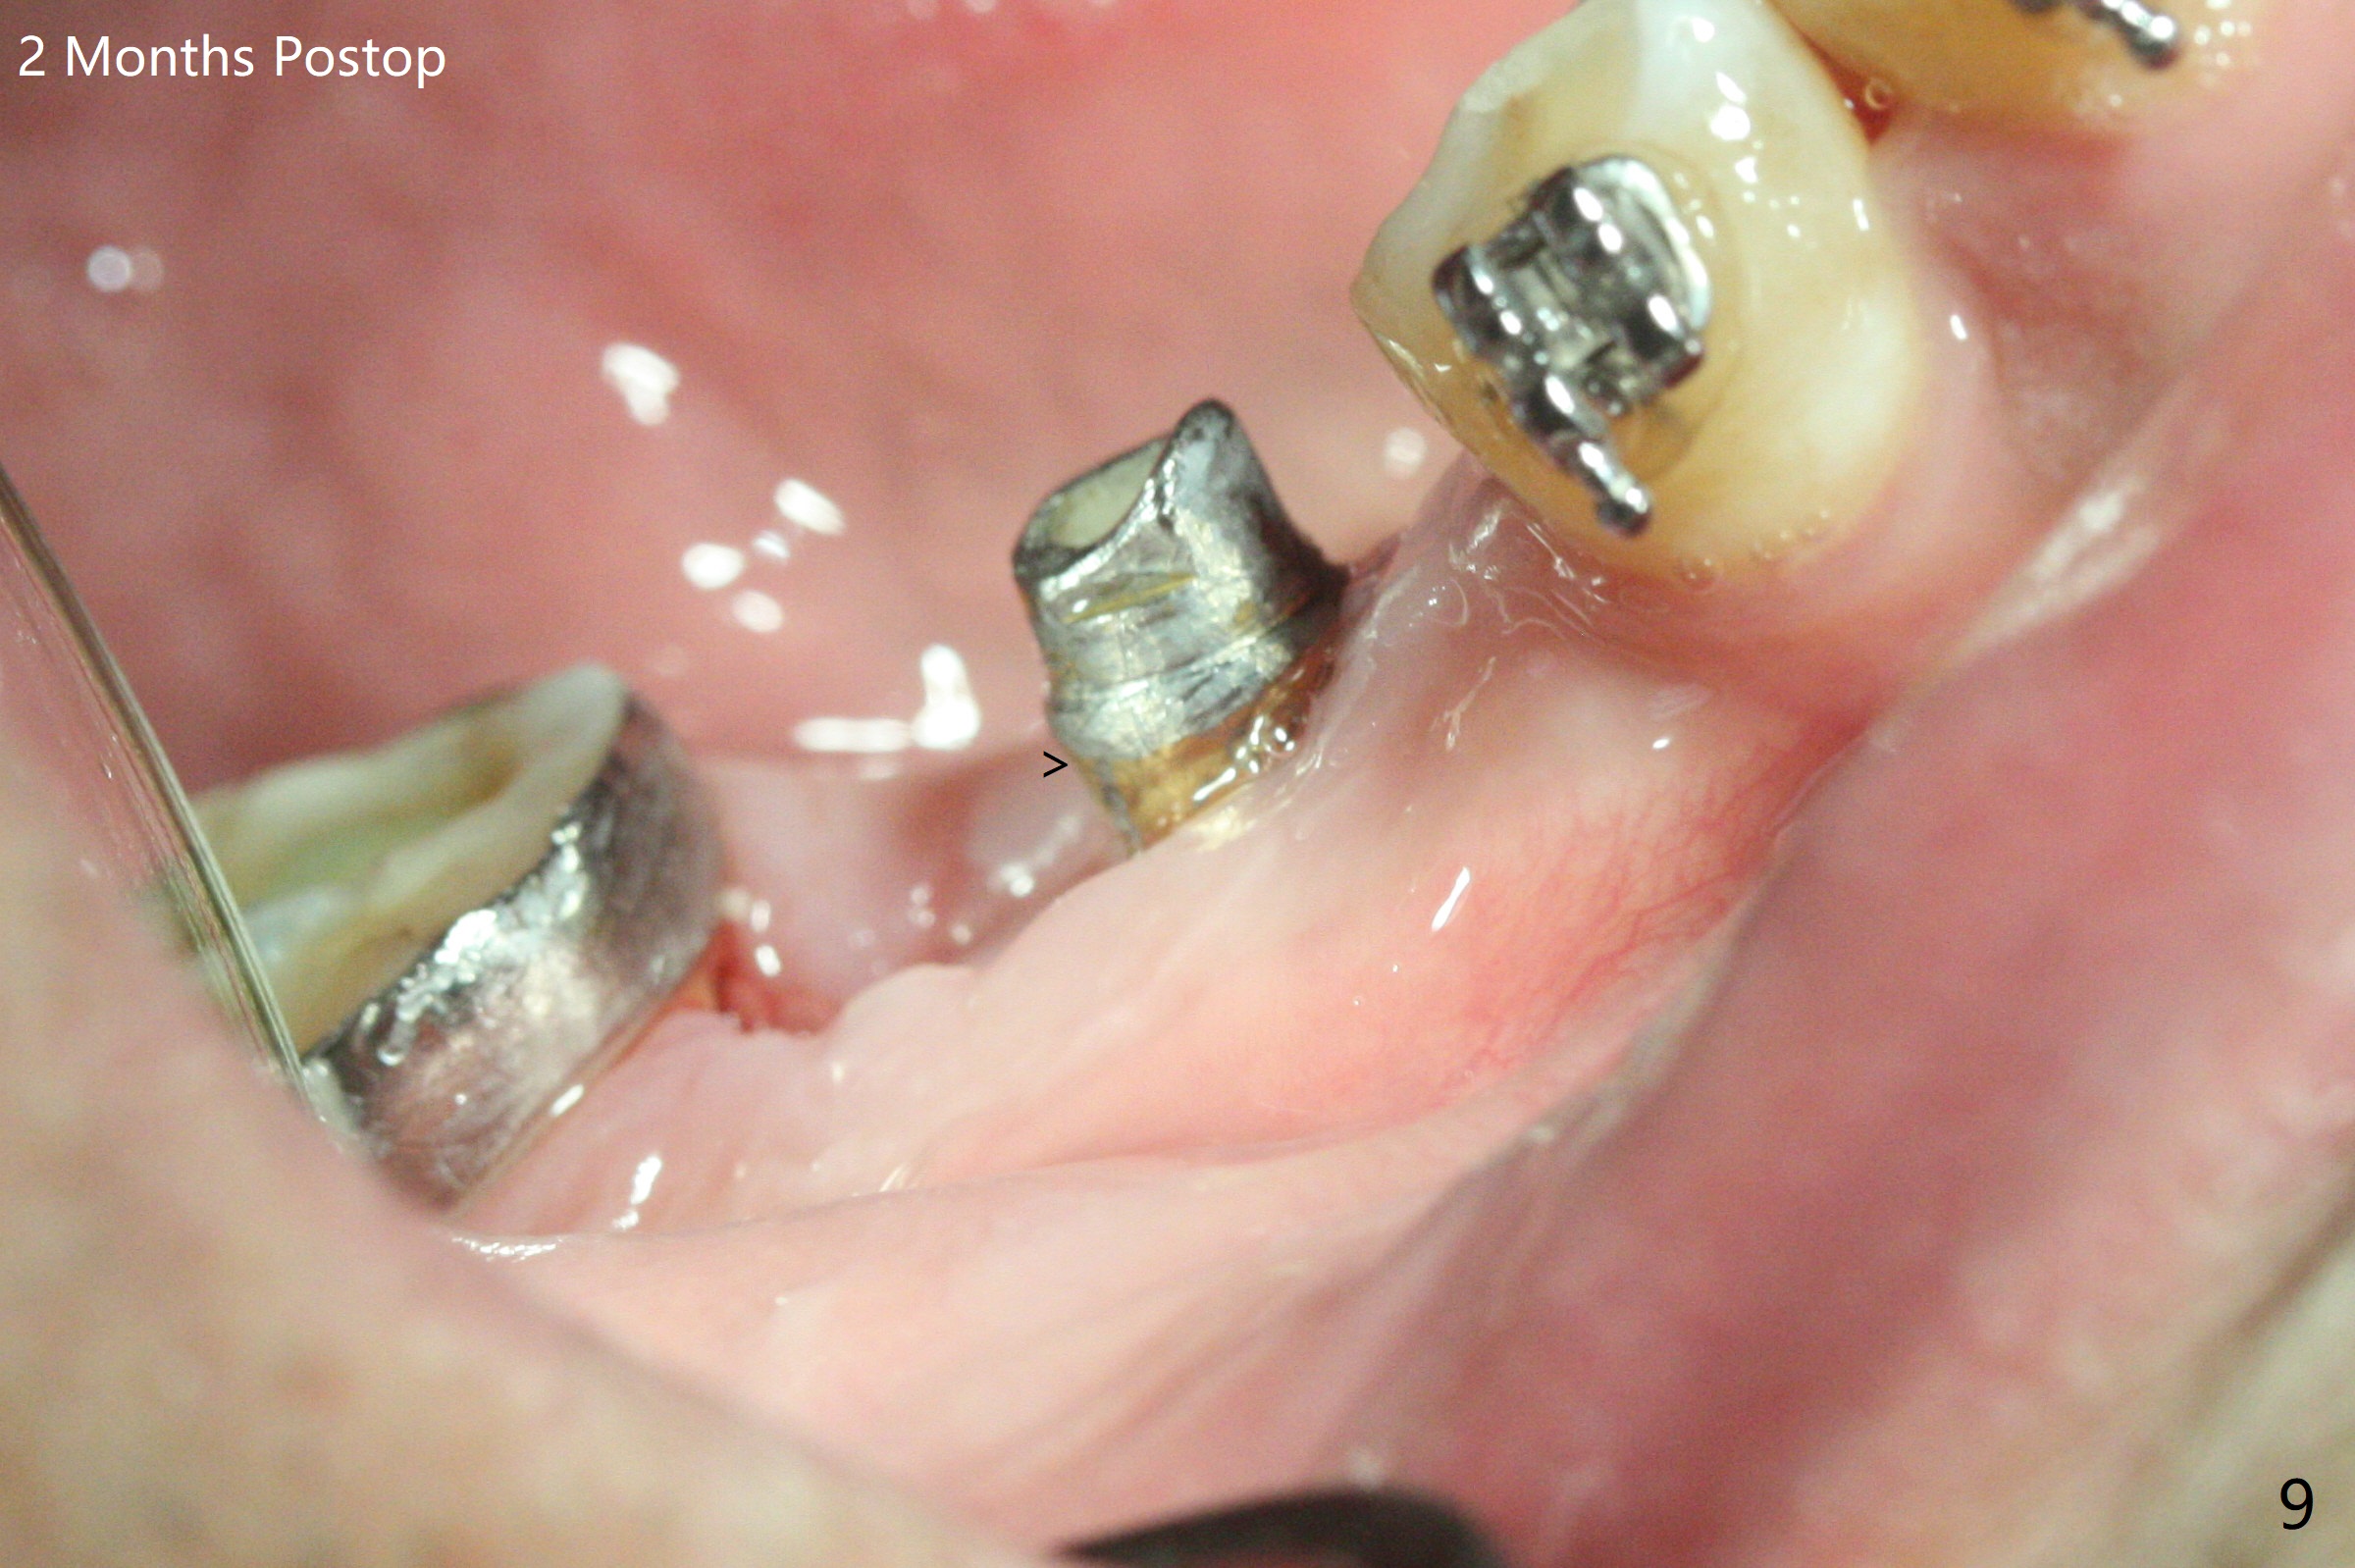

35岁男牙齿矫正后2年5个月右下6远中深龋,拔除后,近中根尖肉芽组织(图零(术前CT冠状切面):*)刮除疼痛,必须阻滞麻醉才能控制疼痛,可能与下牙槽神经分支(图零:红箭头)有关。原先准备在近中牙槽窝近中种植(5x11.5mm),术中发现近中牙槽窝种植好像方便,位置不错,不由自主在那里开始钻洞,由于牙槽窝深,钻洞必须13毫米(图一(接近神经:红虚线)),之后发现钻洞(图二(术前CT3D长轴切面(黑色:近中,远中牙槽窝)):红圆圈)不够理想,使用Lindamann Bur将钻洞往颊侧近中移动(图二:箭头),最终在这方面结果可以(图三,三’,四),虽然接近神经,术后没有神经麻痹。放置粘性骨粉(图四:*),PRF膜,4-0 PGA缝线(图五),最后使用树脂敷料(图六:A)。后牙垂直空间少,术后一周需要降低树脂敷料高度(图七)。术后一个月取出敷料,牙槽窝愈合,植体平台远中稍微暴露(图八),准备一个月后制作临时牙冠。术后两个月植体远中没有暴露,但是基台远中边缘太高了(图九:>),换成6x4毫米愈合基台。下个月换成袖短的修复性基台,安置临时牙冠,牵拉7。舌侧cleats之间放置power chains,颊侧power hooks。其实术后4个月安置临时牙冠和band(图十),牙冠牙合面加高,这样7可以无阻挡移动(图十一:*;16x22 arch wire)。7远中放置power hook行不通,因为末端碰到颊侧前庭牙龈,造成创伤。只好用7颊侧原有牵引勾,在6近中安置一个短的power post (? 图十:箭头),按常规post往下,之间放置12毫米closed spring。如果post往上安置,7牙根牵引可能更有效?近中牵引一个月,第二磨牙前移大约2毫米(图十二:^),稍微近中倾斜,closed spring从12毫米更换到9毫米,舌侧换新的power chains x 4。下一个预约,用sensor 1拍摄根尖片证实第二磨牙近中倾斜,然后在它远中16x22钢丝安放power hook,下缘向颊侧弯曲,避免接触接触粘膜。